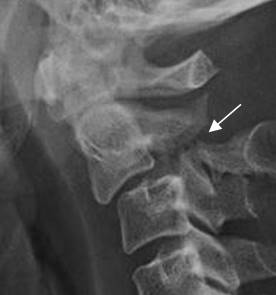

Fig 188. Fractura de Hagman.

Rx lateral. Fractura en los elementos posteriores de C2, con anterolistesis GI de C2, sobre C3.